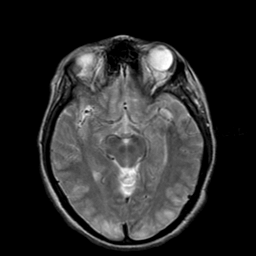

Hypertensive Encephalopathy, overlay -- Slice #10